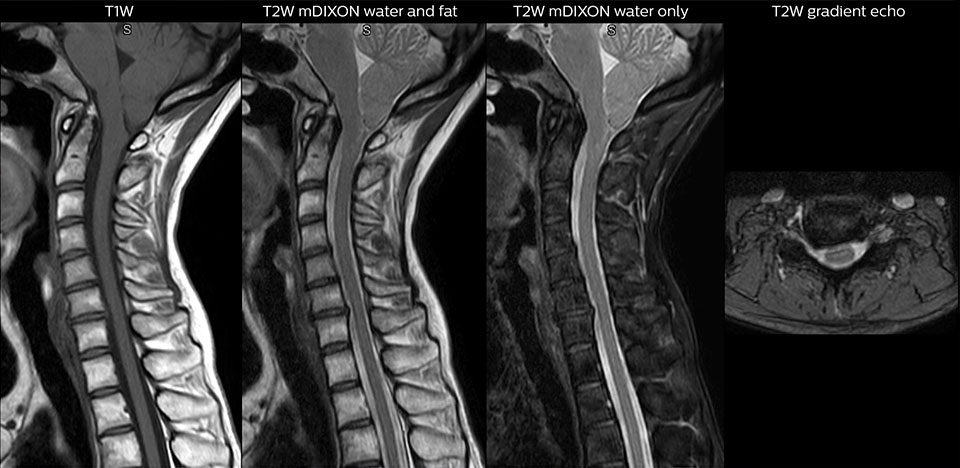

“We use mDIXON TSE extensively in our spine imaging in the emergency room,” says Dr. Karis. “It’s particularly nice in that it is very robust with regard to susceptibility type of problems that would come up with traditional spectral fat-saturated images; these problems are essentially eliminated with the mDIXON technique. In our ED environment it’s really nice to have the fat-free imaging that goes along with the mDIXON technique.

“For the thoracic and cervical spine routine non-contrast exam, for example, we perform one mDIXON T2 TSE sequence, which provides us with two outputs: the fat-and-water-together T2-weighted images, as well as the water-only sagittal T2-weighted images. And then we also perform an axial gradient echo exam.”

Cervical spine routine exam

This patient presented with headache that was worse with neck flexion and we see a Chiari 1 malformation with low-lying cerebellar tonsils as well as some degenerative cervical thrombolytic change.